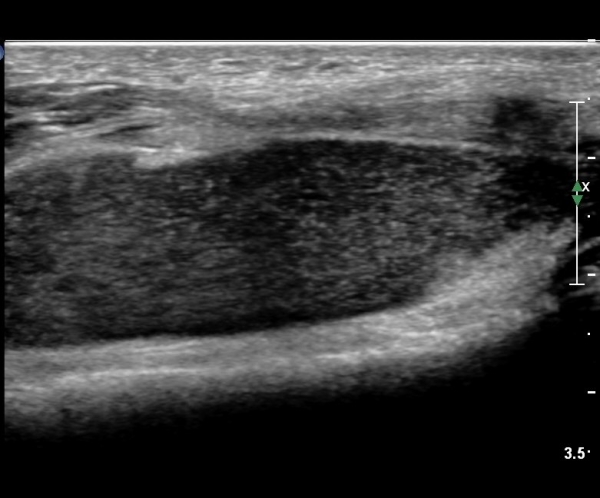

¹«¸­ Àü¸éºÎ Á¾´Ü¸é°Ë»ç¿¡¼­ °üÀý³» ¼ö¾×Àú·ù°¡ °üÂûµÇ´Âµ¥ ¼ö¾×Àú·ù Ç¥Ãþ¿¡ °í¿¡ÄÚ Áö¹æÃþÀÌ °üÂûµÊ(»çÁø 2, 3)

¹«¸­ Àü¸éºÎ Ⱦ´Ü¸é°Ë»ç¿¡¼­ °üÀý³» ¼ö¾×Àú·ù°¡ °üÂûµÇ´Âµ¥ ¼ö¾×Àú·ù Ç¥Ãþ¿¡ °í¿¡ÄÚ Áö¹æÃþÀÌ °üÂûµÊ(»çÁø 4, 5)